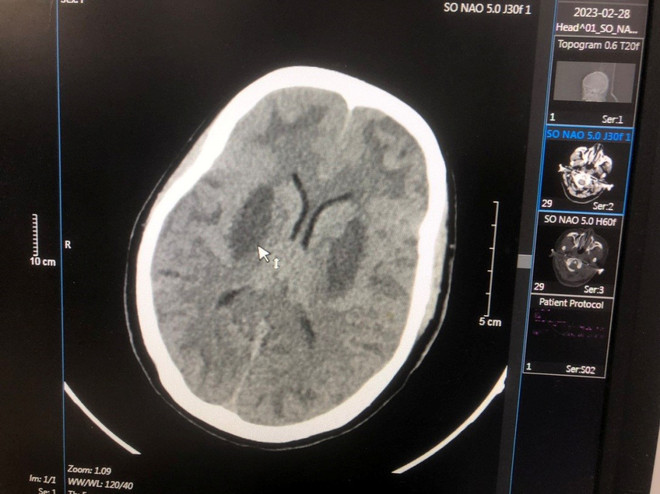

Bệnh nhân nặng thứ hai là Triệu Văn N. 17 tuổi (nam) dân tộc Dao, quê Cao Bằng, vào viện ngày 24/02/2023. Bốn ngày trước khi vào viện, bệnh nhân thấy khó thở, mệt, mờ mắt, lơ mơ, hôn mê, ngừng thở. Bệnh nhân được đưa đến Bệnh viện đa khoa tỉnh Bắc Ninh cấp cứu. Sau đó, N. được chuyển tới Trung tâm Chống độc Bạch Mai trong tình trạng hôn mê, tụt huyết áp, nhiễm toan chuyển hóa nặng, tổn thương não nặng hai bên, nồng độ methanol trong máu là 125 mg/dL, không có ethanol. Bệnh nhân đã được cấp cứu điều trị hồi sức giải độc lọc máu, hiện tri giác có cải thiện nhưng não vẫn tổn thương và phù não nhiều, tổn thương mắt.

Bệnh viện Bạch Mai thông tin vụ nhiễm độc methanol tại Bắc Ninh ảnh 2Hình ảnh tổn thương não của BN Triệu Văn N. (Ảnh: PV/Vietnam+)